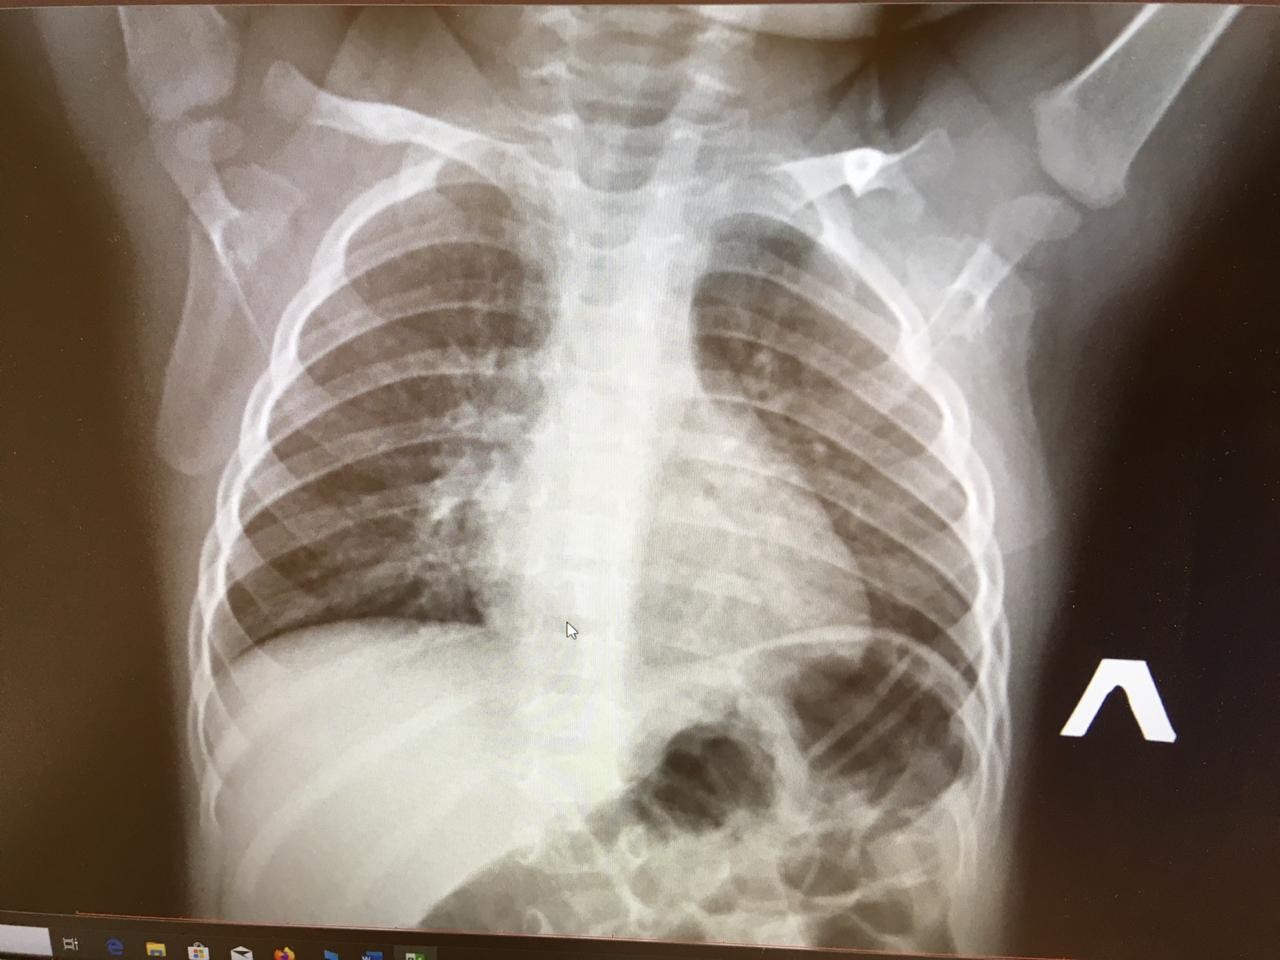

Нормальная рентгенограмма легких: что нужно знать